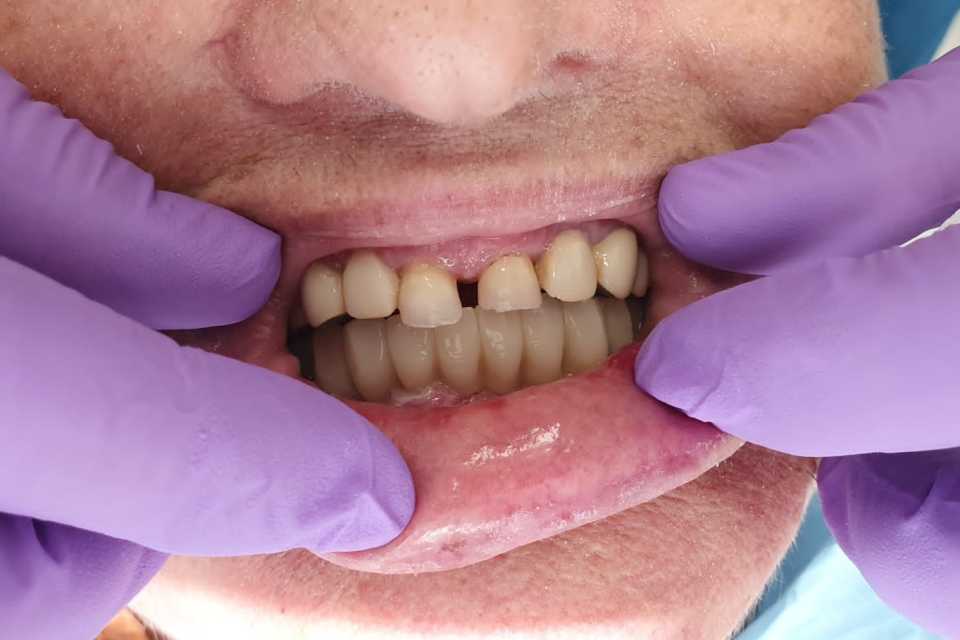

Pacienta, în vârstă de 65 de ani, se prezintă în cabinet acuzând dureri în timpul masticației, mobilitate dentară, halitoză și un aspect inestetic.

Planul de tratament a inclus extracția dinților parodontotici la nivelul mandibulei și inserarea a 5 implanturi dentare Mega-Gen AnyRidge cu conexiune multiunit, urmată de protezarea acestora cu o lucrare fixă, înșurubabilă, din ceramică pe suport de zirconiu.

La nivelul maxilarului, s-au efectuat extracțiile dinților parodontotici, tratamentul laser și chirurgical al leziunilor parodontale, urmate de reabilitarea protetică prin realizarea a două lucrări fixe din ceramică pe suport de zirconiu.